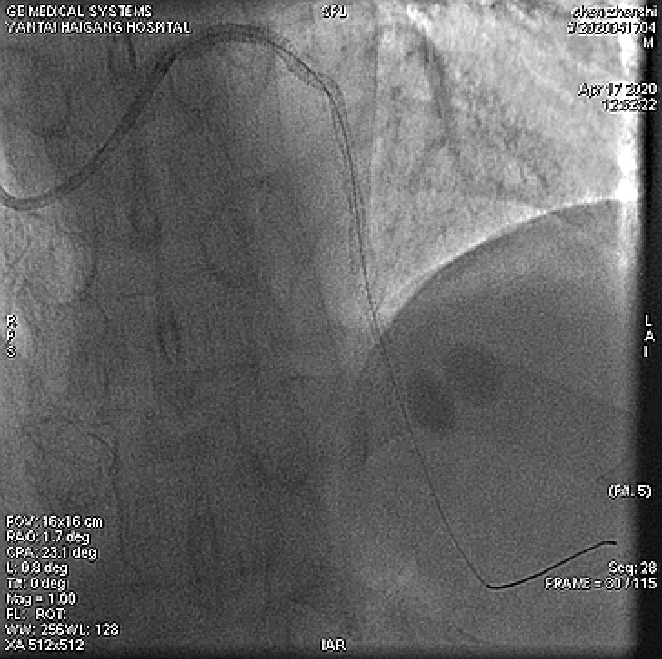

4月17日介入治疗结果如图所示:

文章插图

根据造影结果及患者病情 , 决定优先处理前降支病变 , 择期处理右冠;

分别送导丝至前降支及第一对角支 , 送2.0mm×15mm预扩球囊对病变部位进行充分预扩张处理 。

于前降支中段、左主干-前降支近段依次置入PROMUS ELement 2.5mm×38mm、PROMUS Element3.0mm×38mm支架共2枚 。

复查造影前降支支架以远可见99%局限狭窄 , 于前降支远段置入Firebird 22.5mm×23mm支架1枚 , 并给予后扩张 。

患者手术过程中无明显不适症状 , 术后安返病房 。